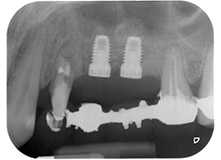

lesión periodontal apical en la pieza dental 24

Fig. 1: En una paciente de 58 años, la radiografía previa a la intervención mostraba una lesión periodontal apical en la pieza dental 24, así como una pérdida horizontal de hueso alveolar en el segundo cuadrante.

Mujer de 58 años de edad, que además es una apreciada colega y amiga, y se quejaba de dolor y de un aumento en la movilidad del pilar del puente de la pieza dental 24. También había inflamación periodontal, con bolsas de una profundidad de 7 mm en sentido mesiobucal y más de 12 mm en sentido distal, así como furcación de tercer grado. Asimismo, la radiografía reveló una lesión periodontal extensa alrededor de la región apical de la pieza dental 24 (figura 1) tratada previamente con endodoncia (alio loco).

Un año antes, las piezas dentales 25 y 26 se habían extraído por razones traumáticas y endo-periodontales antes de la colocación del puente. Se diagnosticó una lesión endo-periodontal combinada en la pieza dental 24, pero su componente etiológico principal no estaba claro. La paciente declaró su voluntad de mantener el pilar del puente de las piezas 24 y 27 y afirmó que no aceptaría una prótesis extraíble final, ni siquiera provisional. Por lo tanto, se acordó intentar por todos los medios conservar ambos dientes, a pesar del mal pronóstico que mostraban las pruebas radiológicas y clínicas.